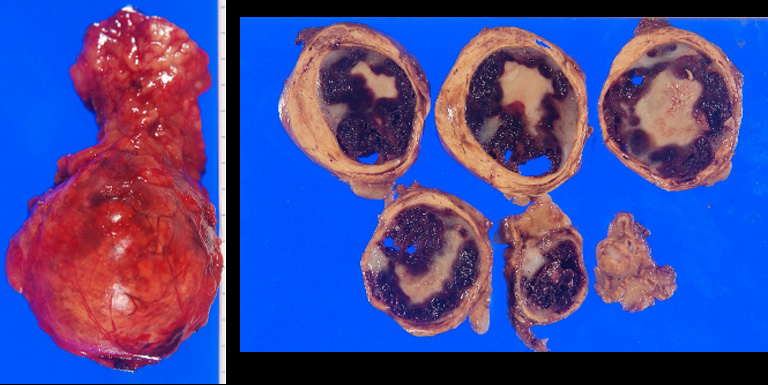

【手術】

腹腔鏡下右副腎摘除術

副腎血管腫

【病理】

Cavernous hemangioma of right adrenal gland

副腎髄質組織に中等大、類円形の血管増生よりなる海綿状血管腫の像を認める。一部では大型に拡張した静脈内に新鮮及び器質化血栓の形成を伴う。副腎組織に異常はない。悪性所見はない。